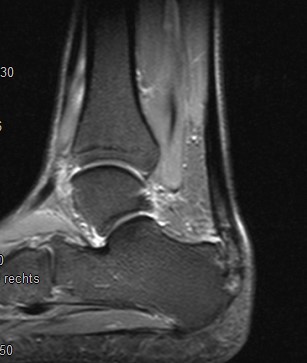

Abbildung 3: Komplette Ruptur Plantaraponeurose und Therapie

Kasuistik: Frau, 45 Jahre.

Abb. 3a: Komplette Ruptur der Plantaraponeurose im MRT als Ursache der Beschwerden deutlich erkennbar.

Abb. 3b: Im präop Röntgenbild kein Fersensporn sichtbar.

Abb. 3c: MRT postoperativ, Knochenanker zur Refixation der Plantarfaszie.

Abb. 3d: Röntgenbild postoperativ, Knochenanker zur Refixation der Plantarfaszie.

Zum Lesen der Bildbeschreibung und zur Vollansicht bitte die Bilder anklicken. Bilder: Dr. Manfred Thomas, Augsburg.